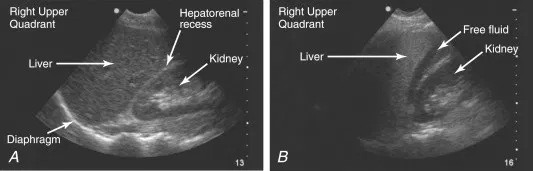

Liquide libre abdominal

extended FAST : Focused Assessment with Sonography for efast Trauma

extended FAST : Focused Assessment with Sonography for efast Trauma